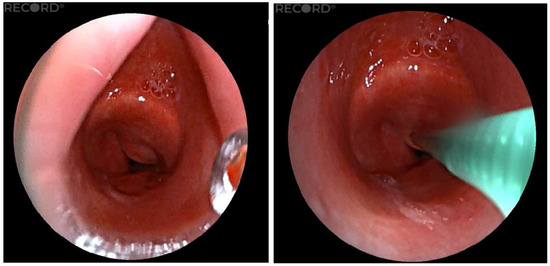

A 37-year-old patient, who was quadriplegic as a result of tick-borne meningoencephalitis, with a long-term tracheostomy, tracheal stenosis, and dependence on full-time nursing care, was indicated for consideration of the removal of the tracheostomy cannula. We used the LJ device to accurately measure the distance of the stenosis from the vocal cords and the length of the stenosis inside the trachea. We measured the distance of the stenosis from the cords to 2.9 cm, and we also quantified the length of the stenosis in the trachea to 1.5 cm (Figure 5). Based on these findings and a multidisciplinary board decision, we indicated this patient for end-to-end tracheal resection with reconstruction of the stenotic area.

Figure 5. Measurement of the length of the stenotic portion of the trachea.